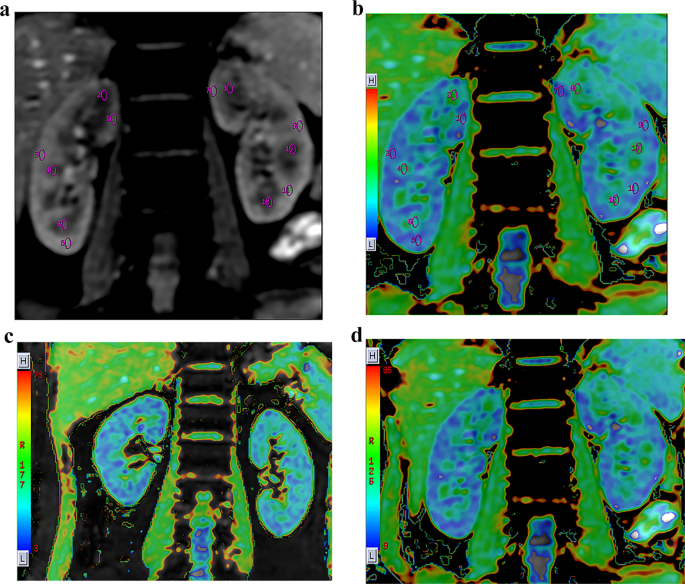

After completion of the scanning sequences, the raw imaging data were transferred to a workstation (Advanced Workstation 4.6), where the R2* values were calculated using BOLD software within the Functool toolkit. Two independent observers blinded to participants’ clinical data independently delineated elliptical regions of interest (ROIs) on grayscale images using a standardized protocol13 as follows: (1) A coronal image at the central level of the renal hilum in which the boundary between the renal cortex and medulla could be clearly discerned was selected for analysis. (2) Oval-shaped ROIs were positioned in the upper, middle, and lower sections of both the cortex and medulla for each kidney. (3) The diameters of the ROIs were kept within the boundaries of the thickness of the renal cortex as displayed on the original image, with each ROI covering an approximate area of 20–40 mm2. (4) Special care was taken to avoid the peripheral edges of the kidneys, the junction between the cortex and medulla, the renal sinus, and any large blood vessels. (5) The R2* values for the renal cortex and medulla were reported as the mean of the measurements taken from the ROIs delineated within the upper, middle, and lower sections. Schematic illustrations of the ROIs are presented in Fig. 2A-B.

Schematic representation of ROI placement and representative R2* maps. (A) Grayscale image demonstrating precise ROI positioning within the renal cortex (R:1,3,5; L: 7,9,11) and medulla (R: 2,4,6; L: 8,10,12). (B) Corresponding parametric R2* map with identical ROIs superimposed (validating parenchymal localization). (C) R2* map of a representative PA patient showing elevated cortical R2* (left > right). (D) R2* map of a healthy volunteer demonstrating physiological corticomedullary R2* gradient. Color scale: R2* values in s−¹ (blue: low oxygenation; red: high oxygenation). All images acquired at 3T with identical parameters. ROI, regions of interest; PA, primary aldosteronism.

Intra- and intergroup comparisons of R2* values

Across all subjects, the R2* values in the renal cortex were significantly lower than those in the medulla (p < 0.01). For PA patients, the R2* values were greater in the left kidney for both the cortex and medulla than in the right kidney. However, among the HCs, the R2* values did not differ significantly between the two kidneys. Furthermore, the R2* values in the cortex of the left kidney (L-Cortical R2*) of PA patients were substantially greater than those in the HC group. These results are presented in detail in Tables 2 and 3, and representative R2* maps for PA patients and healthy controls are depicted in Fig. 2.